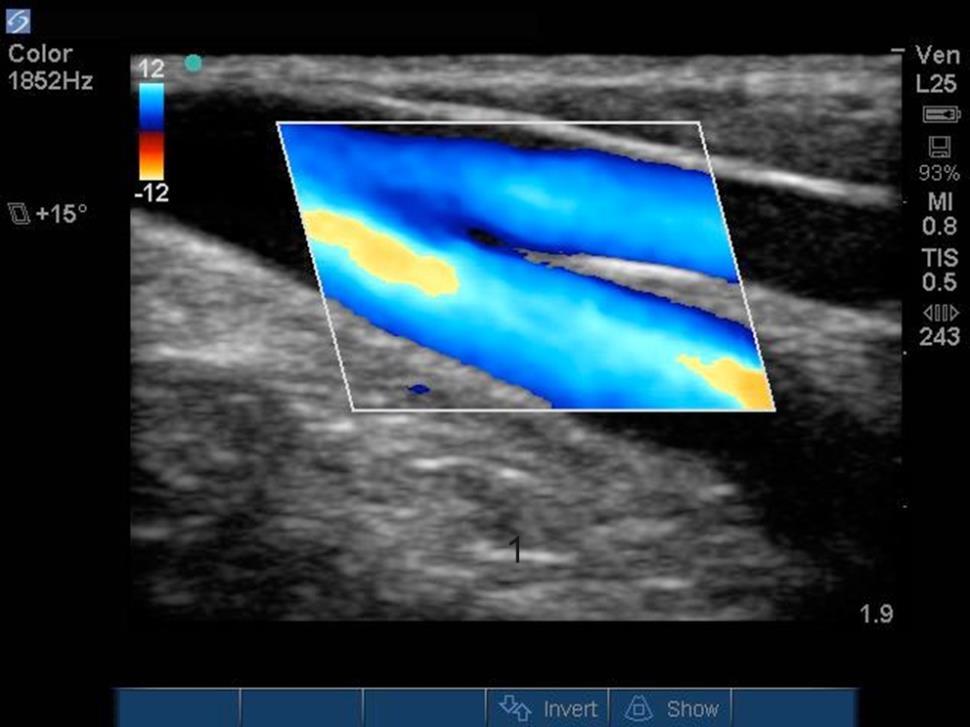

外周 IV (PIV) 静脉彩色血流图像